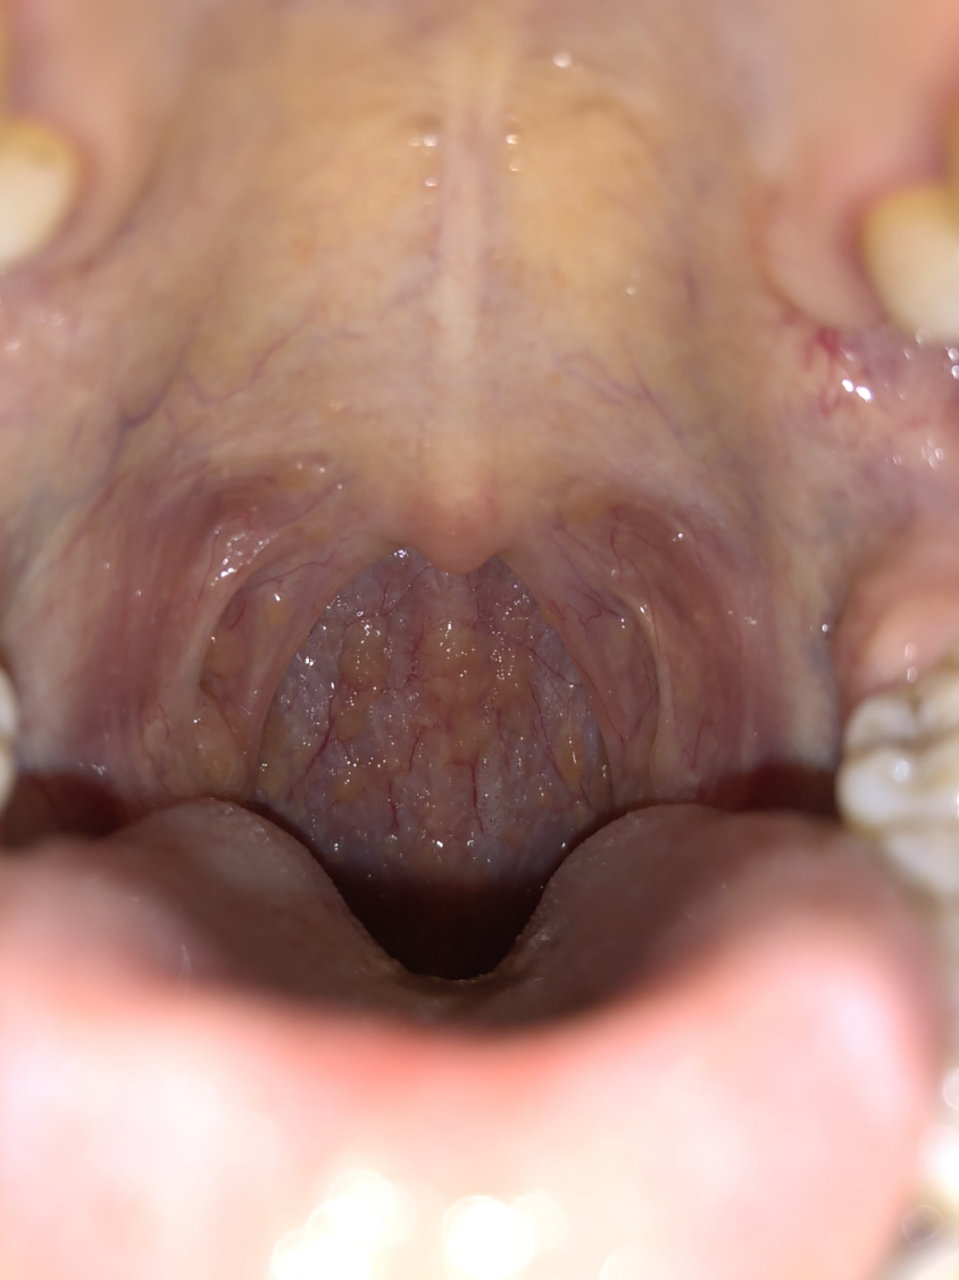

慢性咽炎患者通过口腔可以观察到咽喉黏膜有明显发红,肿胀的症状.

千万别把滤泡性咽炎当成慢性咽炎治 滤泡性咽炎的主要症状实际上是当